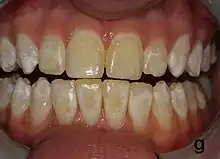

It appears as a range of visual changes in enamel[4] causing degrees of intrinsic tooth discoloration, and, in some cases, physical damage to the teeth. The severity of the condition is dependent on the dose, duration, and age of the individual during the exposure.[1] The "very mild" (and most common) form of fluorosis, is characterized by small, opaque, "paper white" areas scattered irregularly over the tooth, covering less than 25% of the tooth surface. In the "mild" form of the disease, these mottled patches can involve up to half of the surface area of the teeth. When fluorosis is moderate, all of the surfaces of the teeth are mottled and teeth may be ground down and brown stains frequently "disfigure" the teeth. Severe fluorosis is characterized by brown discoloration and discrete or confluent pitting; brown stains are widespread and teeth often present a corroded-looking appearance.[1]

The adequate diagnosis of fluorosis can be diagnosed by visual clinical examination. This requires inspection of dry and clean tooth surfaces under a good lighting.[6] There are individual variations in clinical fluorosis manifestation which are highly dependent on the duration, timing, and dosage of fluoride exposure.There are different classifications to diagnose the severity based on the appearances. The clinical manifestation of mild dental fluorosis is mostly characterised a snow flaking appearance that lack a clear border, opaque, white spots, narrow white lines following the perikymata or patches as the opacities may coalesce with an intact, hard and smooth enamel surface on most of the teeth.[7] With increasing severity, the subsurface enamel, all along the tooth becomes more porous. Enamel may appear yellow/ brown discolouration and/ or many and pitted white-brown lesions that look like cavities. They are often described as "mottled teeth".[8] Fluorosis does not cause discolouration to the enamel directly, as upon eruption into the mouth, affected permanent teeth are not discoloured yet. In dental enamel, fluorosis causes subsurface porosity or hypomineralizations, which extend toward the dentinal-enamel junction as the condition progresses and the affected teeth become more susceptible to staining. Due to diffusion of exogenous ions (e.g., iron and copper), stains develop into the increasingly and abnormally porous enamel.[7]